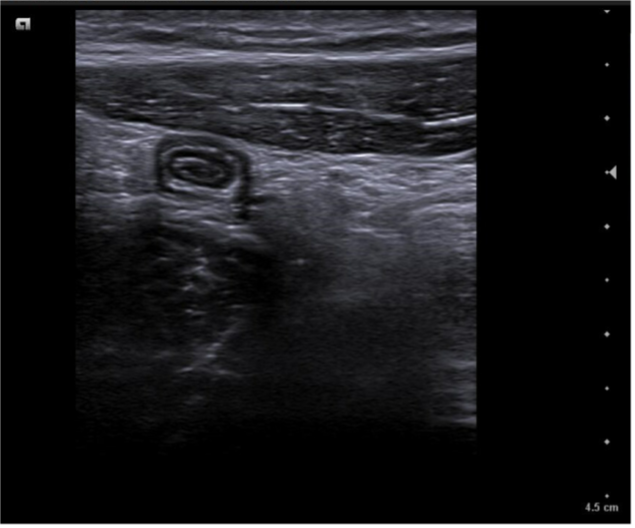

Caso 1. Asa intestinal en FID con poca movilidad (vista con sonda lineal) posible apendicitis.